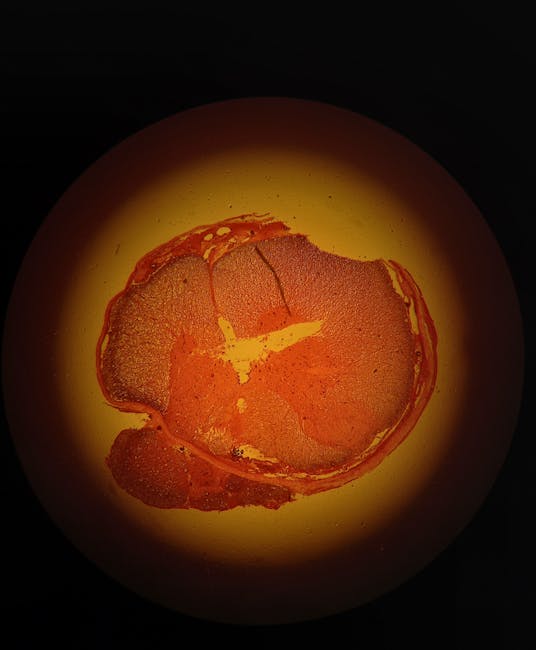

What happens next is equal parts biological tragedy and dark comedy. With the sorting machinery in disarray, vacuoles begin ballooning inside the cell like inflatable pool toys at a bachelor party. These aren't your average storage bubbles. They're massive, relentless space invaders that crowd out essential organelles until, as one researcher put it, the cell resembles a water balloon taped to a fountain. Eventually, the membrane can't take the pressure. Pop. The once fearsome cancer cell goes out with all the dignity of a stepped on ketchup packet.